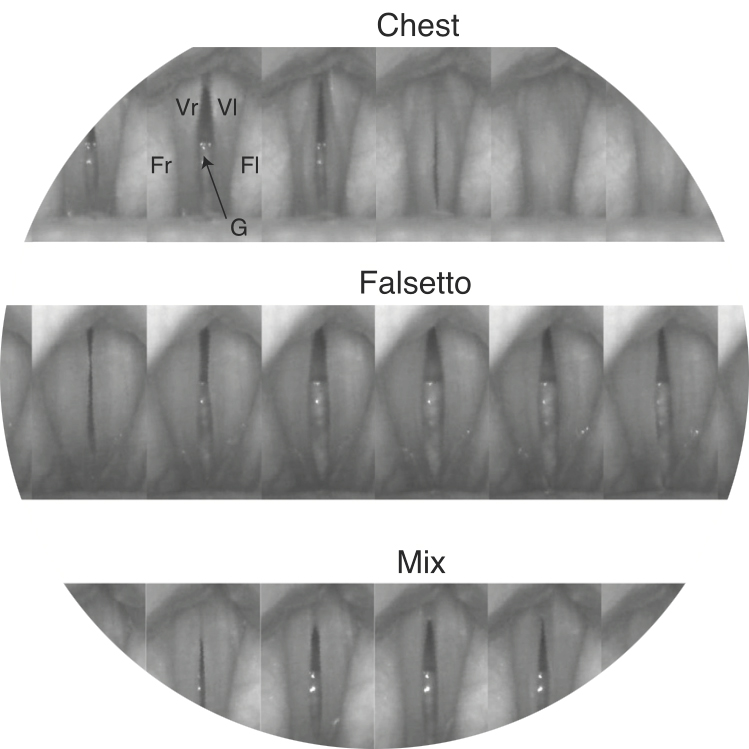

Vi måste prata om mixrösten.